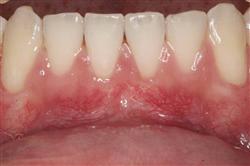

Normally gum tissue surrounds and protects the delicate roots of your teeth. Exposed tooth roots are prone to tooth decay, root canals, discoloration and actual jawbone loss. All of this can lead to tooth loss in advanced cases.

Functional Soft Tissue Grafting replaces the missing gum tissue and protects your teeth. For this reason, soft tissue grafting may be recommended even for back teeth.